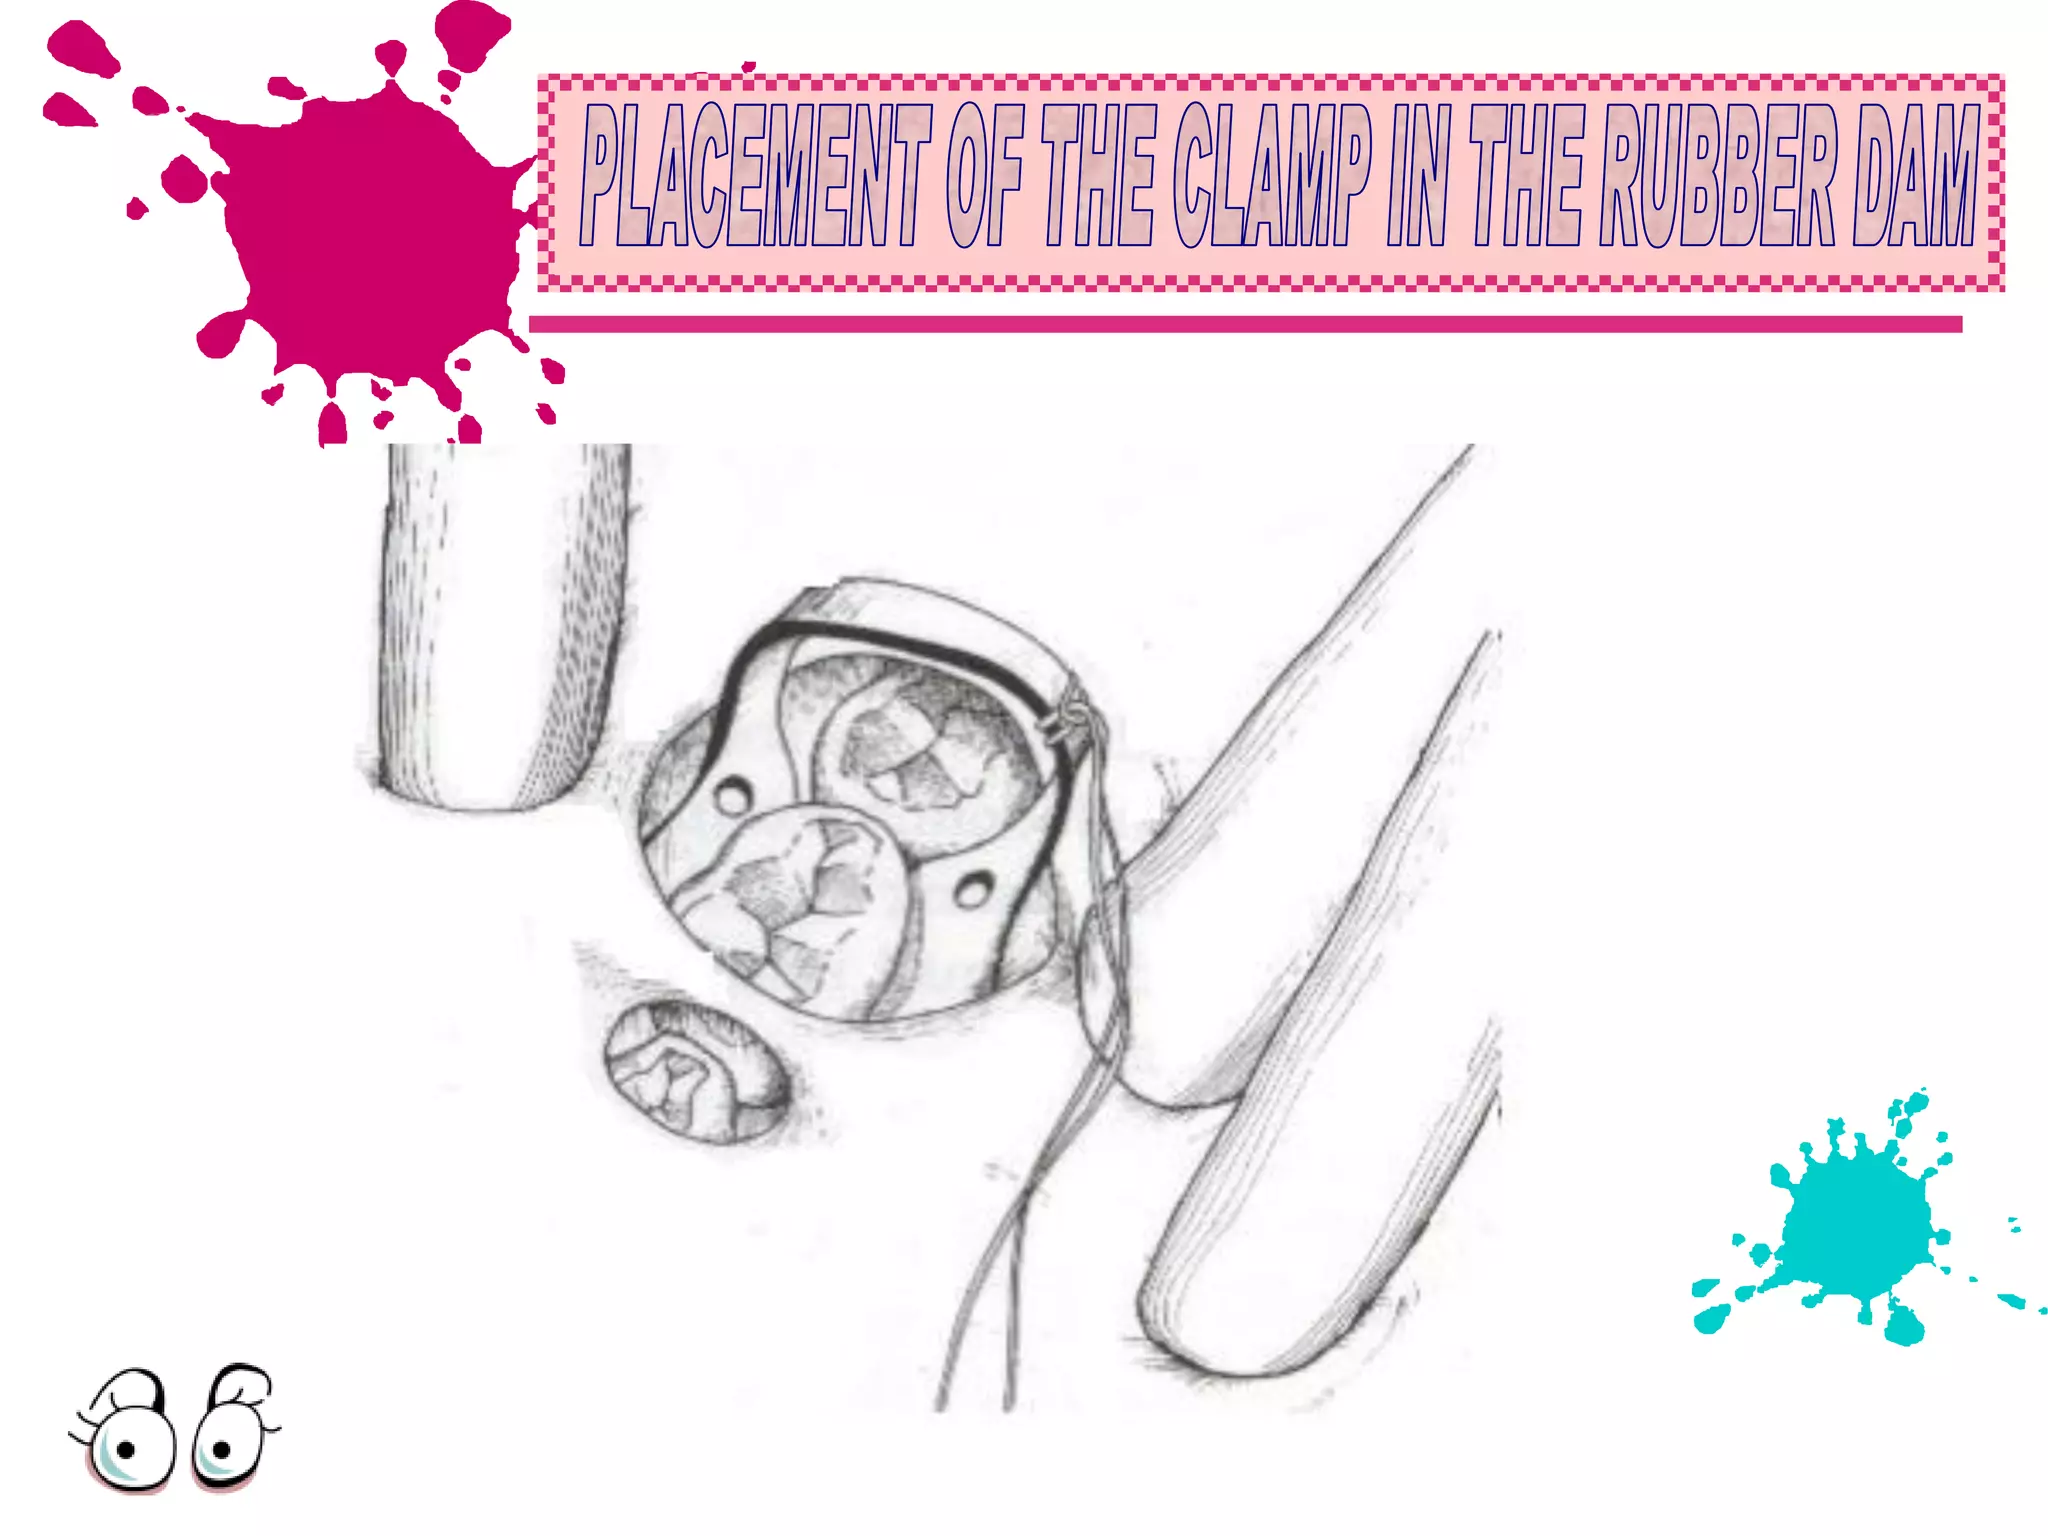

This document discusses the materials and components used for rubber dam isolation in dentistry. It describes the different types of rubber dam materials including color options and napkins to absorb moisture. It also outlines the tools needed such as punches to make holes, templates and stamps to guide hole placement, clamps to secure the dam, and other accessories like wedges and lubricant. Finally, it provides guidance on punching holes for different types of teeth and properly placing clamps in the rubber dam.